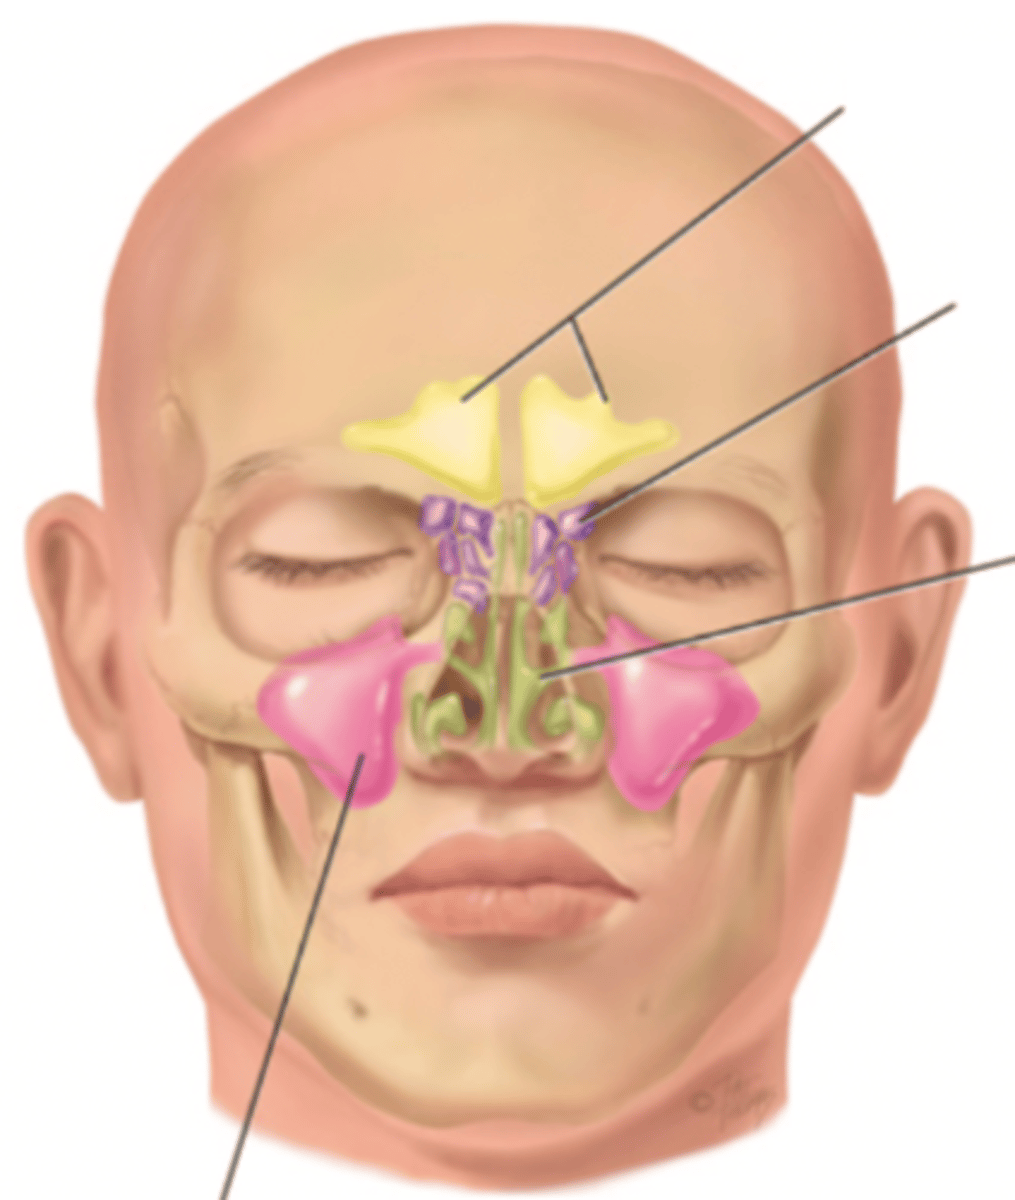

Paranasal Sinuses

- Frontal

- Ethmoid

- Sphenoid

- Maxillary

Frontal Sinus

Cavity within the frontal bone (yellow)

Ethmoid Sinus

Mucosa lined air spaces located above the sphenoid sinus and below the frontal sinus (purple)

Sphenoid Sinus

Sinus above and behind the nose (green)

Maxillary Sinus

Sinus on either side of the nasal cavity below the eyes (pink)